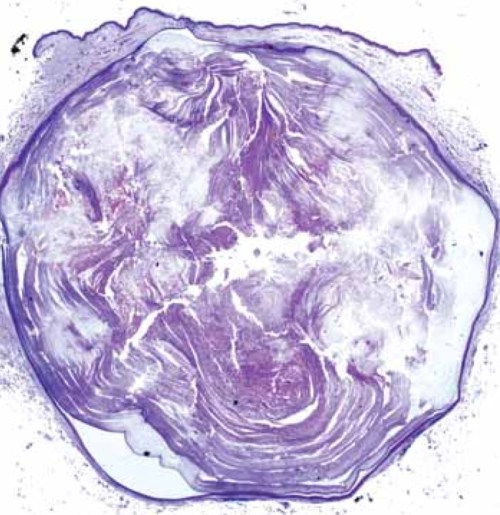

Quiste epidérmico visto al microscopio. Se aprecia fácilmente la cápsula,queratina en su interior y mínimo orificio hacia el exterior.

Extraído de publicación J.L.Rodriguez Peralto, J.Cuevas y R. Carrillo